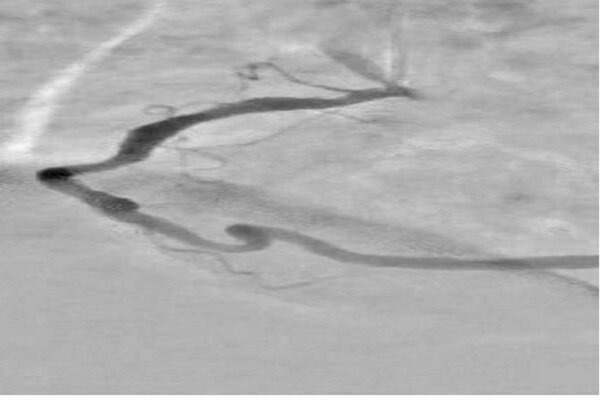

آخوندی با اشاره به دلایل انتخاب این تحقیق، توضیح داد: در آنژیوگرافی قلب، تداخل سایه‌های ناشی از بافت‌ها و استخوان‌های قفسه سینه و همچنین حرکات تنفسی و ضربان قلب باعث می‌شود تشخیص دقیق عروق کرونری دشوار شود. این مسئله منجر به نیاز به تزریق بیشتر ماده حاجب و دریافت دوز بالاتر اشعه توسط بیمار می‌شود.

این دانش آموخته دانشگاه صنعتی امیرکبیر با تاکید بر اینکه نتایج این تحقیق موجب بهبود وضوح تصاویر و افزایش دقت در نمایش عروق کرونری قلب شده است، اظهار کرد: این تحقیق به طور ویژه در جهت ارتقای فناوری پردازش تصویر پزشکی و بومی‌سازی روش‌های نوین شبکه‌های عصبی گامی مؤثر برداشته است؛ چرا که این طرح با کاهش زمان پردازش و افزایش دقت، نسبت به سایر الگوریتم‌های سنتی امکان بهره‌برادری بهتر در حوزه‌های کاربردی را فراهم می‌سازد.

آخوندی ویژگی‌های این طرح را شامل افزایش وضوح عروق کرونری در تصاویر آنژیوگرافی، کاهش نیاز به تزریق مقدار زیاد ماده حاجب و در نتیجه کاهش خطرات مرتبط با آن برای بیمار دانست و افزود: همچنین نسبت به روش‌های سنتی، زمان پردازش تصاویر را به طور قابل توجهی کاهش می‌دهد و می‌تواند حتی با در اختیار داشتن یک تصویر تکی حاوی ماده حاجب نیز عمل اصلاح و پردازش را انجام دهد. در نهایت، بهره‌گیری از فناوری شبکه‌های عصبی عمیق، امکان استخراج و بازسازی هوشمند پس‌زمینه و جداسازی بهتر عروق را فراهم می‌کند و طرح را از نظر علمی و کاربردی در سطح روش‌های نوین پردازش تصویر پزشکی قرار می‌دهد.

وی تاکید کرد: نمونه‌های خارجی مانند روش‌های مبتنی بر RPCA یا MAMR وجود دارند، اما روش حاضر بومی بوده و عملکرد سریع‌تری دارد. در این طرح با حذف نیاز به تصاویر چندزمانه، دوز اشعه دریافت‌ شده توسط بیمار کاهش یافته و فرآیند تصویربرداری ساده‌تر و ایمن‌تر شده است. این روش به دلیل تکیه بر الگوریتم‌های پیشرفته و یادگیری عمیق، پردازش تصاویر را سریع‌تر و به صورت خودکار انجام می‌دهد و در عین حال دقت بالاتری در تفکیک عروق و پس‌زمینه ارائه می‌کند.